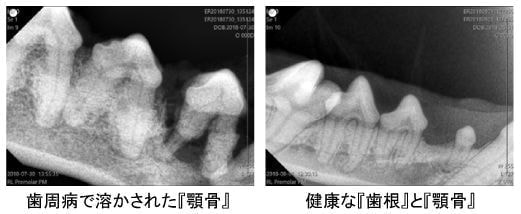

Q4.ハミガキしないとどうなるの?

歯周病が進行すると以下のような症状がみられます。

歯周病が進行し『歯を全部抜いた』という子もみかけるのではないでしょうか。

また、お口周りの症状だけでなく、全身すべての内臓に歯周病菌の毒素が悪影響を与え、様々な病気を引き起こします。

『歯石の影響で心臓病になる』というのは人間だけではありません。

歯石は目に見える表面よりも、歯と歯肉の間のポケット部分が重要です。

ポケットに歯石が沈着し、歯石が後退することで歯周病が進行し、歯と歯肉がダメになります。

- 歯科レントゲン撮影ができないため、抜歯すべき歯が残る

当然ですが、『無麻酔』では適切なレントゲン撮影ができず、抜くべき歯がみつけられません。

そして抜くべき歯を安全に抜くことができず、歯周病の末に顎の骨折を生じることがあります。